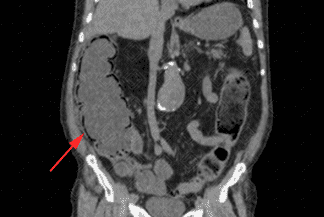

Texto alternativo para a imagem Créditos: Dra. Elazir Mota - Rio de Janeiro/RJ

Descrição das imagens: Tomografia computadorizada do abdome evidenciando importante distensão das alças de cólon ascendente e ceco, em associação com a presença de gás na parede destas alças (setas vermelhas), o que caracteriza a pneumatose intestinal.